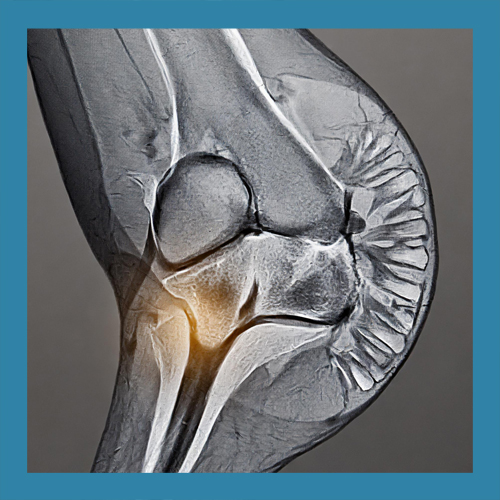

반월상 연골은 무릎 관절 내에 위치한 반달 모양의 연골 조직으로, 관절 사이의 충격을 흡수하고 관절의 안정성을 유지하는 역할을 합니다. 좌우로 각각 하나씩 존재하며, 무릎이 움직일 때 발생하는 마찰을 줄이고 관절 연골의 손상을 예방합니다. 이 조직은 혈액 공급이 제한적이기 때문에 손상 시 자연 치유가 어려운 경우가 많습니다.

반월상 연골 파열의 치료는 손상의 위치와 정도에 따라 다르게 접근해야 합니다. 경미한 파열은 보존적 치료로 충분히 회복될 수 있지만, 심각한 경우에는 수술이 필요할 수 있습니다. 이를 정확히 판단하기 위해 MRI와 같은 정밀 검사가 필수적입니다.